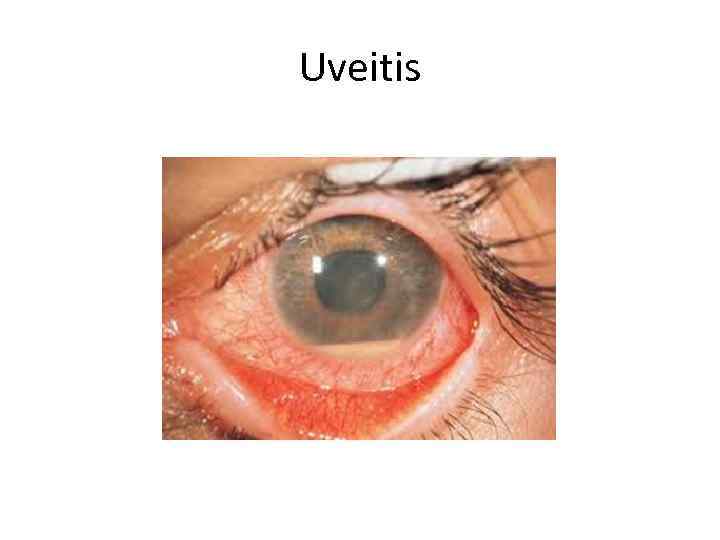

Uveitis

Uveitis